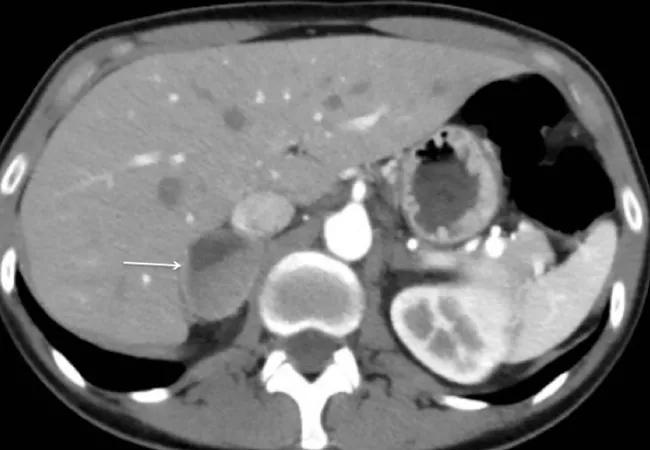

Figure 1. Preoperative CT scan demonstrating the right-sided pheochromocytoma.

A 50-year-old woman who was working overseas for the U.S. government presented at a hospital in Germany in hypertensive crisis. Imaging was performed and the patient was found to have a 4-cm right adrenal mass.

The treating physician contacted Dr. Berber seeking his expertise in adrenal disorders. Dr. Berber coordinated the appropriate workup, which included checking serum and 24-hour urine collections for catecholamines and metanephrines. The patient’s catecholamines and metanephrines were four-fold elevated.